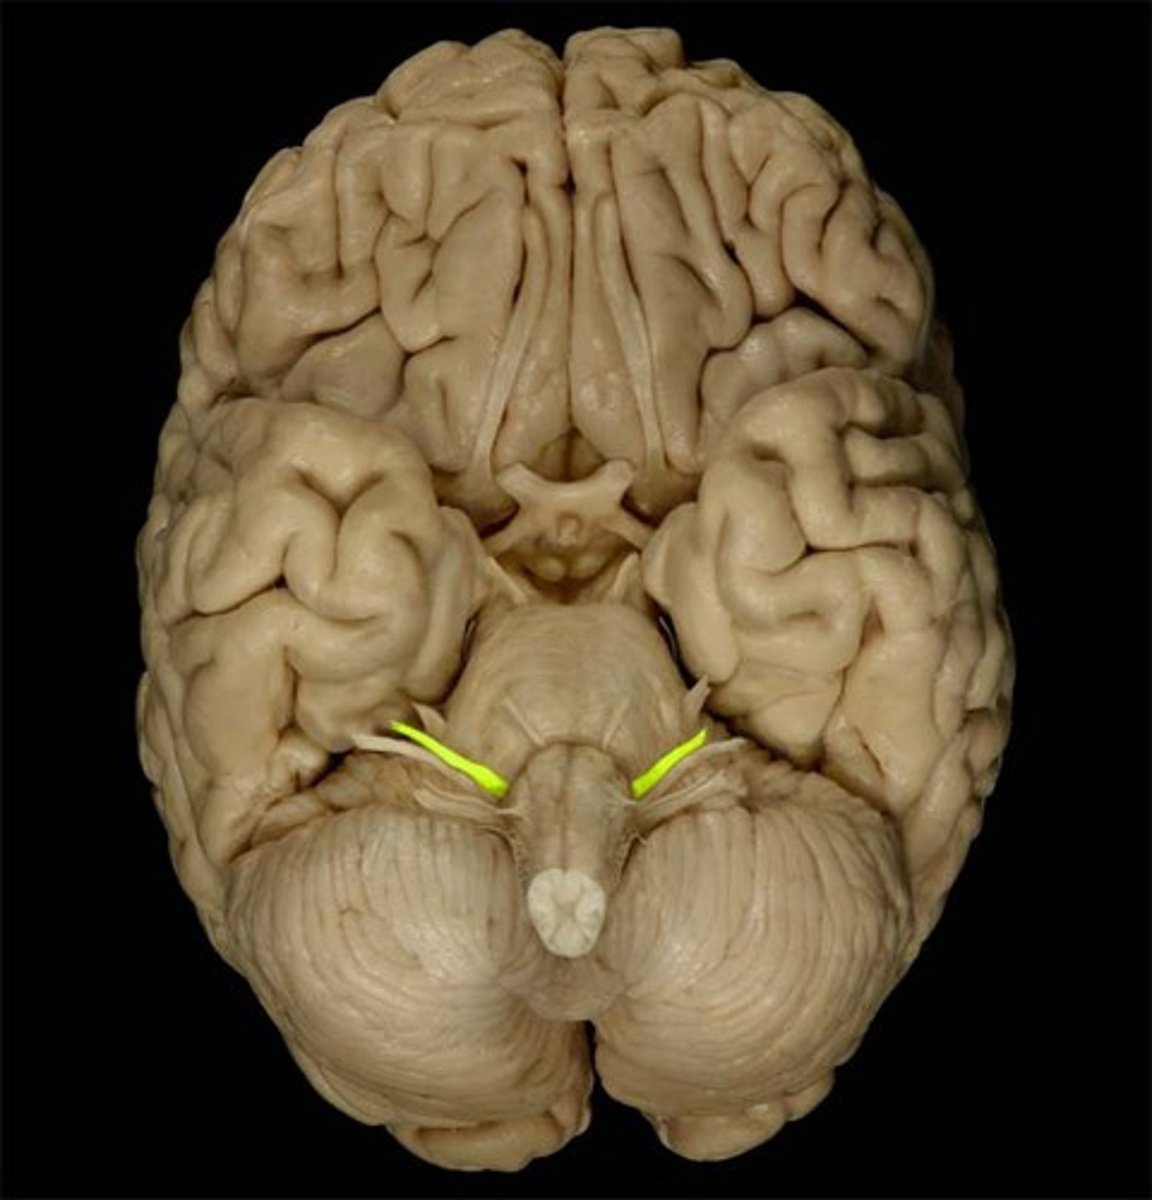

Facial Nerve

Function: mixed (motor, parasympathetic, general sensory)- facial expression, lip articulation, taste on anterior tongue, secretion of saliva and tears

Location: Medulla-Pons junction

Vestibulocochlear Nerve

Function: special sensesory- hearing and balance